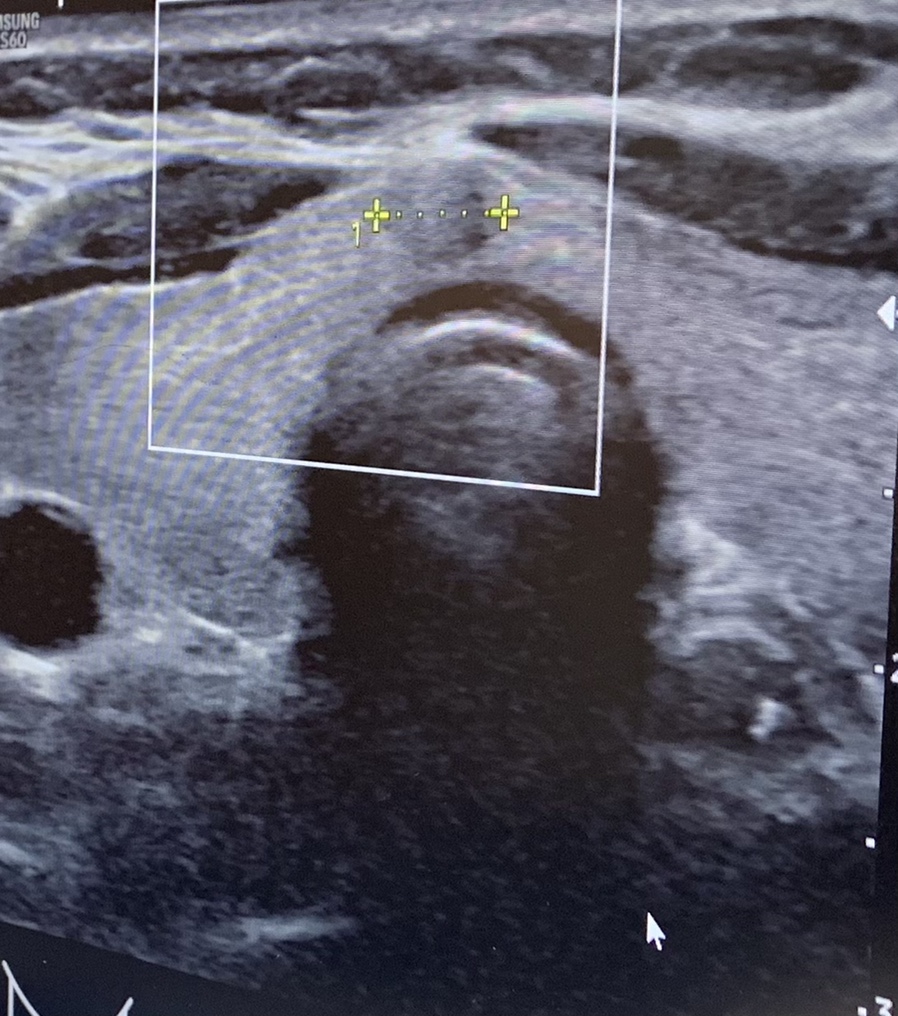

그리고 짠~

저 동글동글한 노란색 표시가 결절이다.

이 후 갑상선 카페에 가입하여 이미 수술을 마친 분이나 앓고 있는 분 등 들었는데, 둥글고 경계가 명확하기 때문에 너무 걱정하지 말라는 것입니다만, 의사의 말에 따라 빨리 검사해 보는 것이 올바른 방법이라고 들었습니다.

“새침하게 검사해도 양성으로 나오는데 위치가 있어야 하는 위치니까” ㅠㅠ… 트룰루… 위치가 림프선 가까운 가운데여서 그런가 봐 쿵쾅쿵쾅…